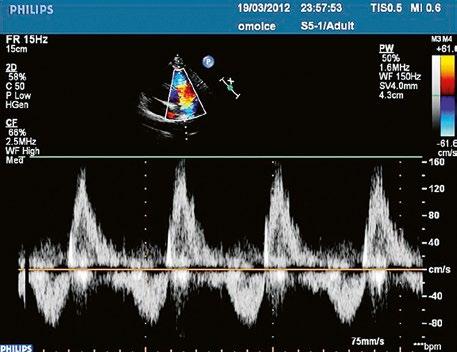

Obr. 45.46 TTE, parasternální krátká osa. V barevném dopplerovském mapování je patrná v diastole významná pulmonální regurgitace po valvulotomii pulmonální stenózy v dětství LK – levá komora, RVOT – výtokový trakt pravé komory

Obr. 45.47 Stejný pacient jako na obrázku 45.46. PW dopplerovské vyšetření ukazuje v RVOT laminární nízkorychlostní zpětný tok při významné pulmonální regurgitaci po valvulotomii pulmonální stenózy v dětství.

Video 45.40 TTE parasternální krátká osa s barevným dopplerovským mapováním, v RVOT je patrná těžká pulmonální regurgitace v diastole (stejný pacient jako na obrázku 45.46 a obrázku 45.47)

pravé komoře a sníženém tepovém objemu. Po provedené balonkové nebo chirurgické valvuloplastice v dětství bývá v dospělosti častá významná pulmonální regurgitace (Obr. 45.46, Obr. 45.47, Video 45.40).